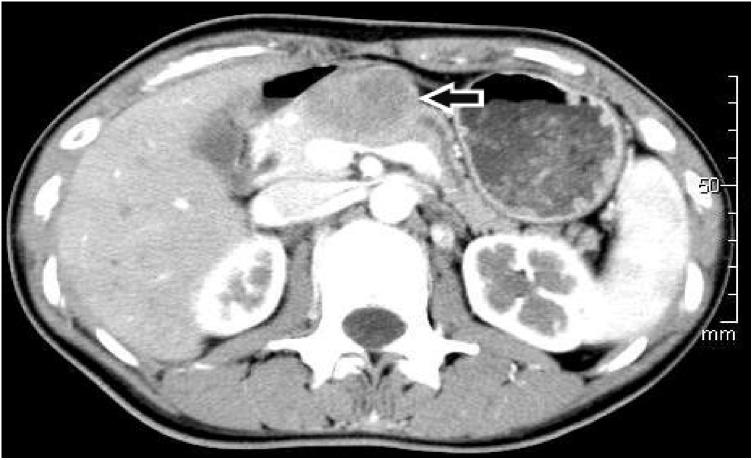

On univariate analysis, a solid component (p < 0.01), septation (p < 0.01), location (p < 0.01), border (p < 0.01), wall enhancement (p = 0.01), lesion margins (p < 0.01), pancreatic atrophy (p = 0.04), and a cystic wall (p < 0.01) were all significantly different between benign and premalignant or malignant cysts. On multivariate analysis, only a solid component (p < 0.01) and septation (p < 0.01) were significant.

A thin cystic wall, uniform homogeneity, a clear border, the presence of septation, pancreatic atrophy, and the absence of both wall enhancements and solid components were more frequently seen in benign cysts. A thick wall, lack of homogeneity, the presence of wall enhancements and solid components, absence of septation, only a small degree of pancreatic atrophy, and unclear borders were more frequent among premalignant or malignant cysts. The only CT features to differentiate benign from premalignant or malignant cysts were a solid component and septation.

单因素分析显示,实性成分(p<0.01)、分隔(p<0.01)、位置(p<0.01)、边界(p<0.01)、壁强化(p=0.01)、病变边缘(p<0.01)、胰腺萎缩(p=0.04)和囊壁(p<0.01)在良性囊肿与癌前或恶性囊肿之间均存在显著差异。多因素分析显示,只有实性成分(p<0.01)和分隔(p<0.01)具有显著性。

良性囊肿更常表现为薄壁、均匀一致、边界清晰、存在分隔、胰腺萎缩,且无壁强化和实性成分。癌前或恶性囊肿更常表现为厚壁、不均匀、存在壁强化和实性成分、无分隔、仅有轻度胰腺萎缩以及边界不清。区分良性囊肿与癌前或恶性囊肿的唯一CT特征是实性成分和分隔。